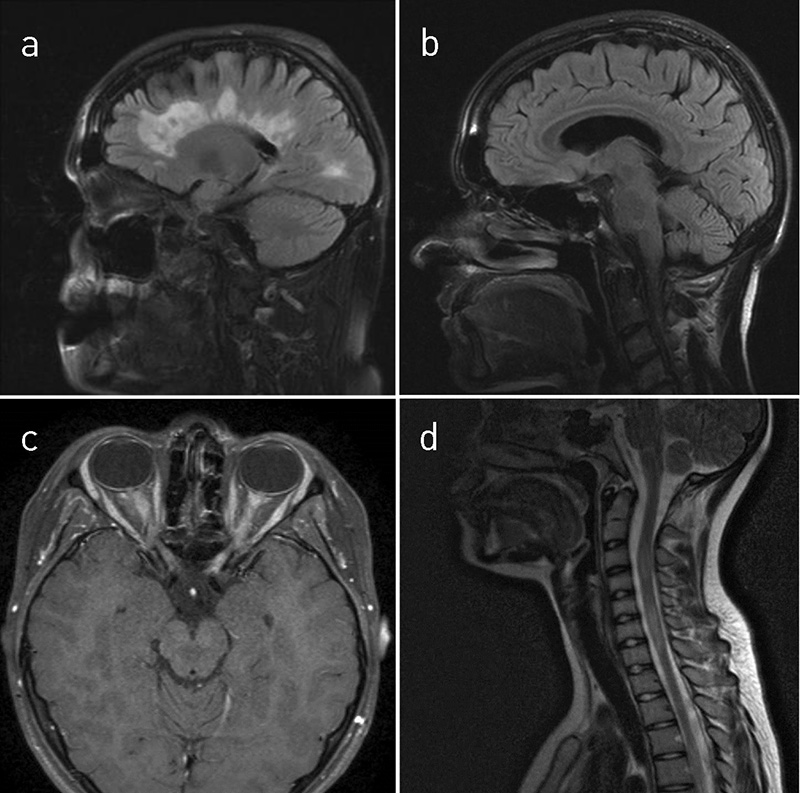

I tillegg til anamnese og klinisk undersøkelse inkluderer utredningen MR-undersøkelse (magnetisk resonanstomografi) av hjerne og ryggmarg, analyse av cerebrospinalvæske, visuelt fremkalt respons og blodprøver (fig 1). Ved neuromyelitis optica kan det påvises et spesifikt antistoff rettet mot akvaporin-4, en osmosedrevet vannkanal (fig 2). Dette finnes i serum hos ca. 75 % av pasientene (2, 11). Antistoffet kan også påvises i cerebrospinalvæsken, men kun forbigående i akuttfasen hos et fåtall av pasientene. Rutinemessig undersøkes derfor kun serum for slike antistoffer. Ifølge europeiske retningslinjer kan det ved høy klinisk mistanke, men negativ akvaporin-4-antistoffprøve være aktuelt å gjenta testen eller teste i cerebrospinalvæsken (12). I Norge utføres disse testene ved Haukeland universitetssykehus og Oslo universitetssykehus, Ullevål.

Typiske MR-funn hos pasientene er sentrale lesjoner i ryggmargen som strekker seg over minst tre vertebralnivåer. Det er vanlig med normal MR-undersøkelse av hjerne ved debuttidspunktet, men opptil 80 % av pasientene kan etter hvert utvikle cerebrale MR-forandringer. Disse er ofte ukarakteristiske og asymptomatiske (12, 13). Bare ca. 10 % har cerebrale MR-funn som regnes som mer typiske for neuromyelitis optica på grunn av lokalisering til områder med høy tetthet av akvaporin-4, som hypothalamus og periakveduktale hjernestammeområder (15) – (18). Til sammenlikning viser MR-undersøkelse av pasienter med multippel sklerose ofte typiske periventrikulære hvitsubstanslesjoner i hjernen samt korte, flekkevise perifere lesjoner i ryggmargen.